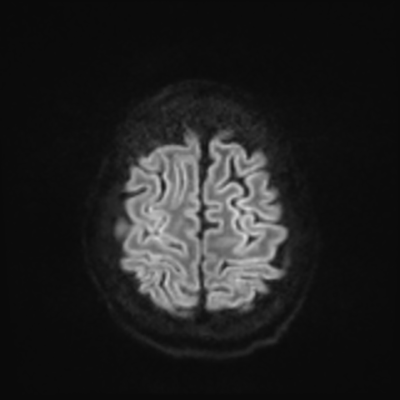

MRI brain (DWI)

MRI brain (DWI) 2/24 2/24

You can clearly see diffuse cortical and basal ganglia diffusion restriction, and that of his deep cerebellar nuclei as well. The right occipital lobe abnormalities are a little more prominent, but then you remember that he is known to have had a right occipital stroke weeks ago.

In reviewing his data, you know that he doesn't have any of the strong predictors of a poor neurologic prognosis. However, based on these findings on MRI, along with the absent reactivity on cEEG, you are able to tell the primary team and the patient's family that he is likely to have a poor prognosis, based on these multiple moderate predictors. Recovery is not completely impossible-- there is more uncertainty with this prognostication than if we were able to get SSEPs-- but you're very worried about his outlook and that any potential recovery would require a very protracted rehabilitation period. Given his high cervical cord injury level, tracheostomy would be required anyway. So, it comes down to whether his family thinks he'd want to pursue these aggressive measures.